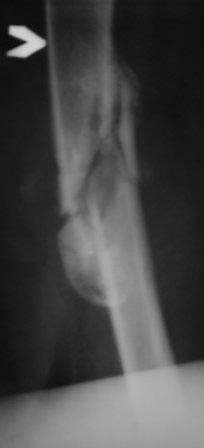

Уважаемые коллеги. Госпитализирован б-ной 47 лет, травма высотная 9 месяцев назад, тогда оперирован и/м остеосинтез ( чрезвертельный перелом не диагностирован) в одном мед.объединение, через 3 месяца почему-то штифт удален. Больной ходит с двумя костылями, ногу не нагружает, выраженная патологическая подвижность в с/з бедра, в обл вертелов патологическую подвижность определить не удается, умеренная отечность всего бедра, укорочение около 4-5см.

В плане в начале дистрактор, после устранения укорочение и репозиции БИОС реконструктивным стержнем( универсальным).